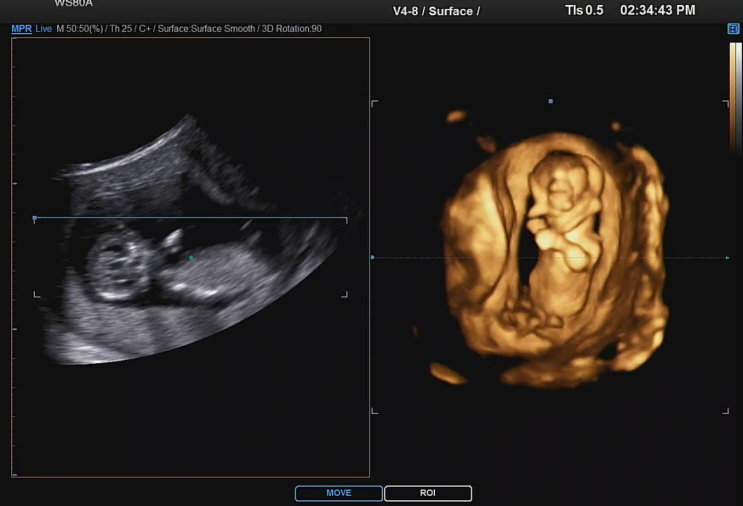

임신 20주차 입체 초음파, 먹고 싶은거 하고 싶은거 다해

급격히 배가 나오기 시작한 20주차 이제 맞는 옷이 없어져서 그나마 하나 있는 치마도 지퍼 열고 입음 남편...